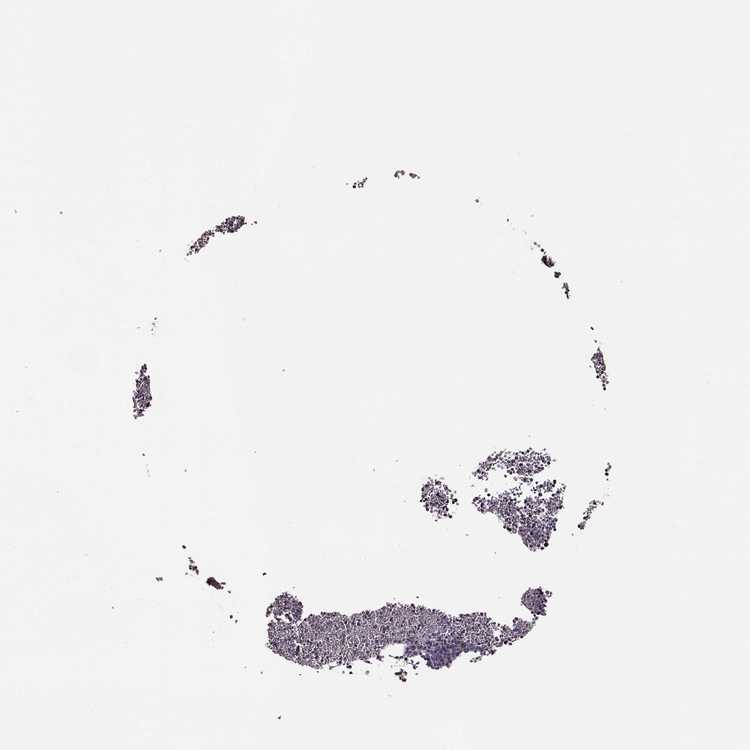

BONE MARROW - Antibody stainingi

Antibody staining in the annotated cell types in the current human tissue is reported as not detected, low, medium, or high, based on conventional immunohistochemistry profiling in selected tissues. This score is based on the combination of the staining intensity and fraction of stained cells.

Each image is clickable and will lead to virtual microscopy that enables deeper exploration of all samples and also displays staining intensity scores, fraction scores and subcellular localization as well as patient and tissue information for each sample.

Antibody HPA070003

Hematopoietic cells Low